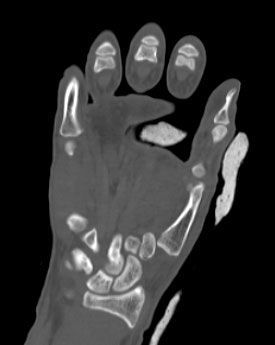

4. Displaced fracture of distal end of the right radius (wrist fracture) in a 63-year-old female.

Treatment. Open reduction internal fixation

I. Before operation, anteroposterior x-ray of the wrist II. Before operation, lateral x-ray of the wrist IIA. Day of procedure, lateral view IIB. Day of procedure, anteroposterior view